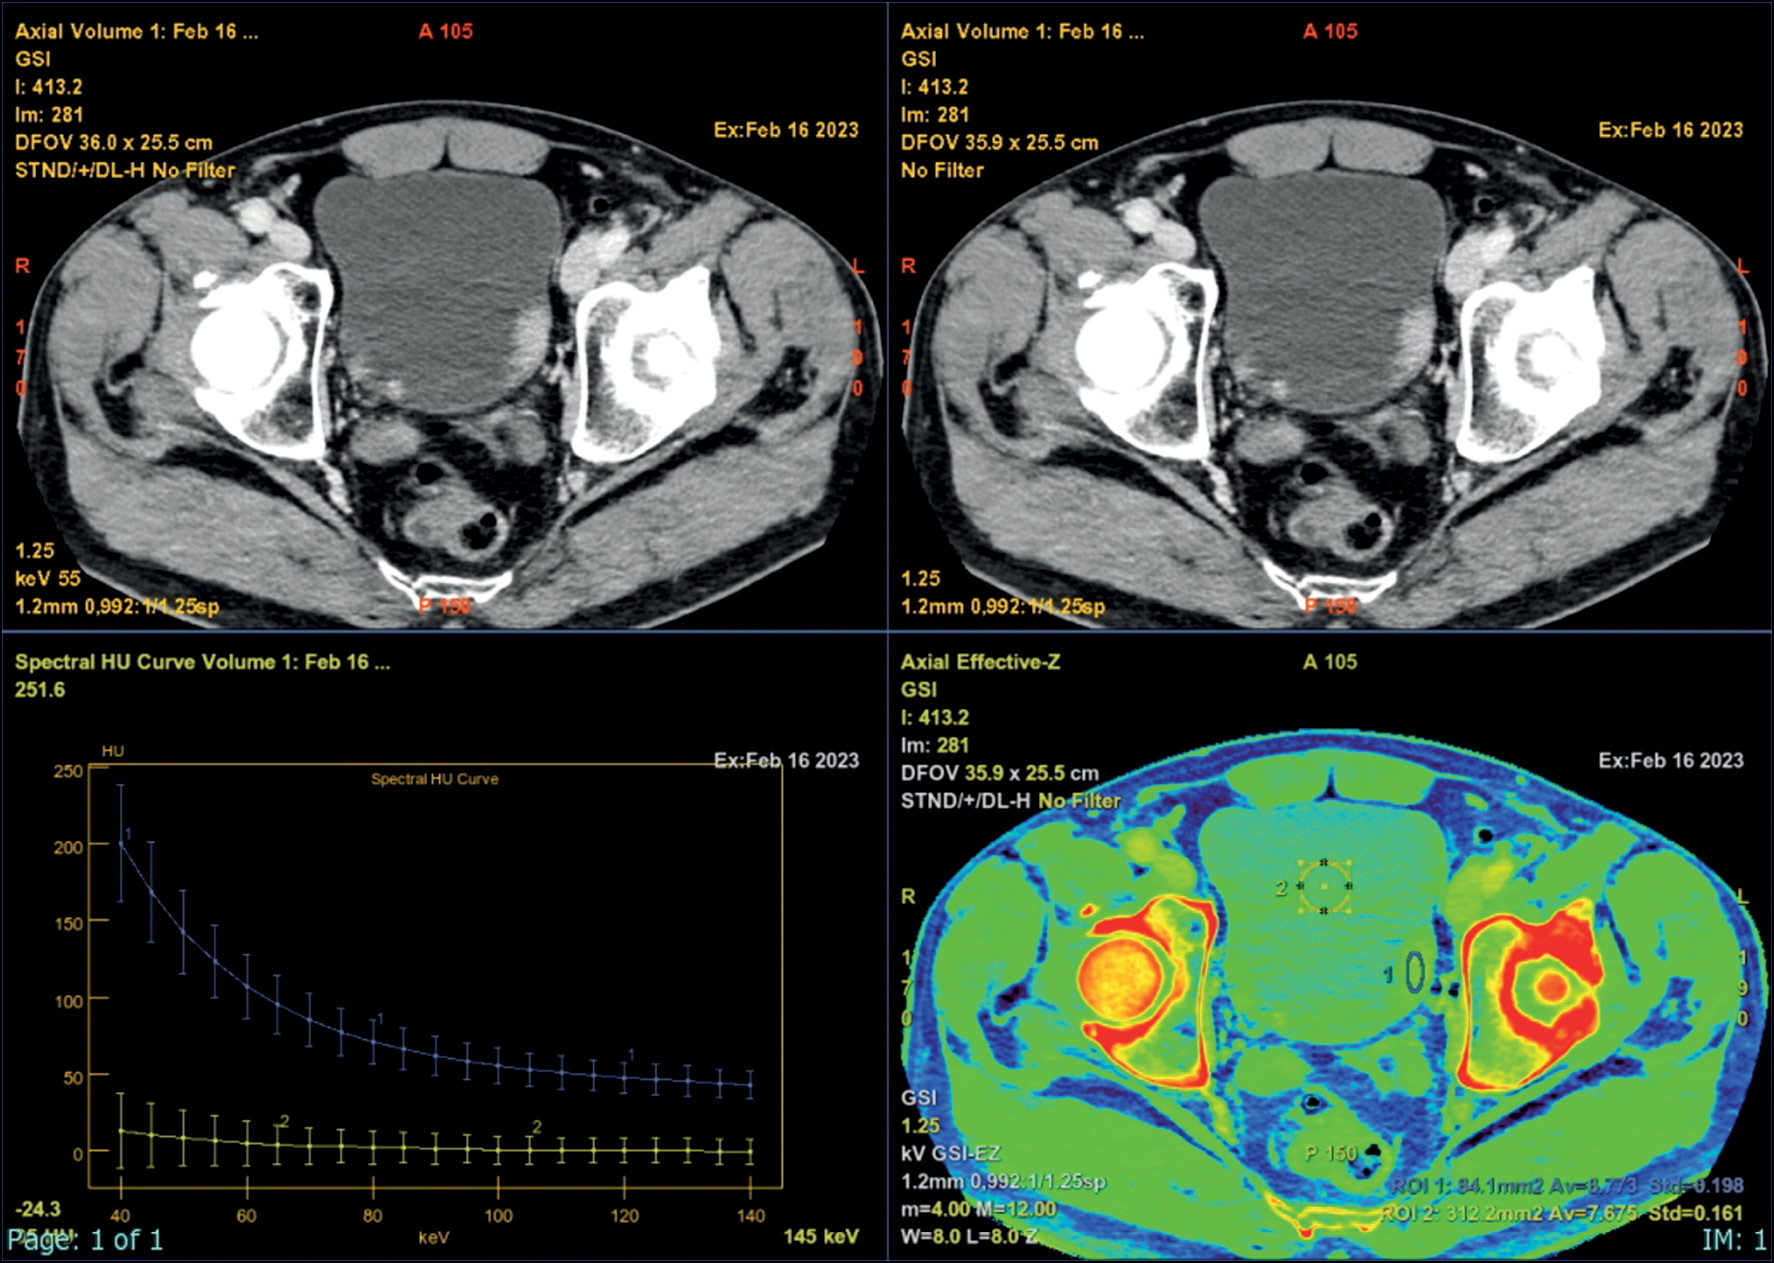

При использовании двух источников излучения с разным напряжением (высоким и низким уровнем энергии) для виртуальных монохромных изображений получают спектральную кривую затухания в зависимости от уровня энергии. Кривую используют для оценки свойств с целью более точного описания очага.

Карта фактических зарядовых чисел применяется для количественной оценки различий материалов и измерения различий в затухании в зависимости от уровня энергии (рис. 3) [34].

Рис. 3. Атомная карта (Zeff) с гистограммой.

Спектральная кривая благодаря её свойствам подходит для более точного описания очага. Например, кривая, построенная для узлового образования стенки мочевого, идёт к максимуму при более низком уровне энергии в кэВ (рис. 4).

Рис. 4. Спектральная кривая позволяет более точно установить характеристики материала, поскольку кривые затухания у разных материалов отличаются. С помощью воздействия при разных уровнях энергии можно дифференцировать материалы на основании различий в коэффициентах затухания одного материала.